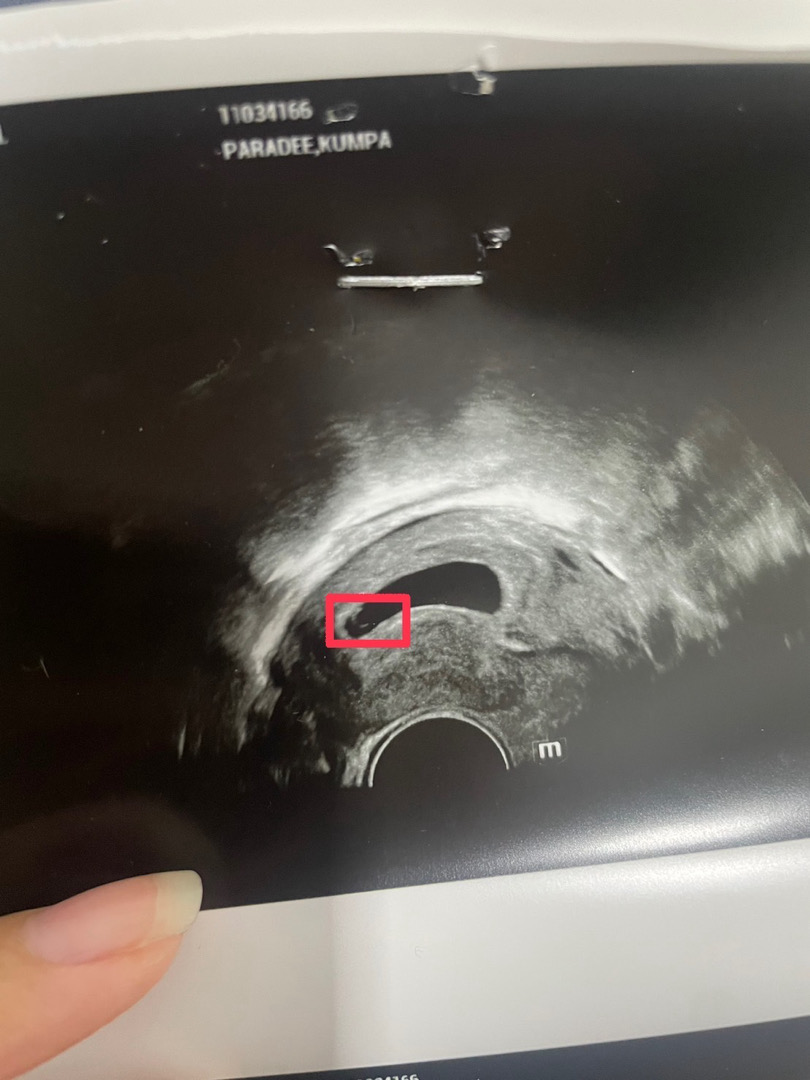

สวัสดีค่าแม่ๆ อยากปรึกษาแม่ๆหน่อยค่ะ ขอเล่าตอนไปแบล็กกราวตอนไปตรวจให้ฟังก่อนนะคะ 24 Dec 23 : อัลตร้าซาวรอบแรก - เจอถุงครรภ์ขนาด 1.4 Cm - หมอชี้ให้ดูไข่แดงจุดๆๆ จิ๋วมาก - หมอแจ้งว่าอายุครรภ์ 5w2d 7 Jan 24 : อัลตร้าซาวรอบ 2 (นับจากครั้งแรกอายุครรภ์น่าจะต้อง 7w2d) - ขนาดถุงครรภ์ใหญ่ขึ้น (หมอไม่ได้แจ้งว่ากี่ Cm) - ยังไม่เจอตัวอ่อน - หมอรีบตรวจมากๆ และบอกไม่เจออะไรเลย แต่เราเห็นแวบๆ (วงไว้ในภาพที่แปะ) สรุปหมอบอกว่าท้องลม และบอกว่ารอบแรกก็ไม่เจออะไรมีแต่ถุงครรภ์ (ตรงนี้หมอพูดไม่เหมือนรอบแรก เราก็งงๆ ช็อคอยู่) ก็คุยกันต่อว่าจะรอให้หลุดเองธรรมชาติ อีก 2 อาทิตย์ไปซาวดูอีกรอบเผื่อเจอโค้งสุดท้าย และไม่ได้จ่ายค่ายบำรุงมาแล้ว คำถามค่ะ 1. ปกติเจอน้องตอนที่กี่วีคคะ 2. เป็นไปได้มั้ยคะที่น้องอาจจะยังเล็กมาก 3. ตอนเจอน้องถุงครรภ์มีขนาดเท่าไหร่คะ 4. แนะนำรพ. หรือคลินิกให้หน่อยค่ะ อยากลองไปตรวจจากที่อื่นบ้าง ปล. อาการปกติทุกอย่าง คลื่นไส้ เวียนหัว เจ็บหน้าอก ปวดท้องเบาๆ เพลียง่าย และไม่มีเลือดซึมค่ะ *ภาพที่แปะไปเป็นภาพที่ซาวครั้งที่ 2 ค่ะ

เราท้อง 6w เจอแค่ถุงตั้งครรภ์ +ไข่แดง (ภาพแบบคุณแม่เลย) ไม่เจอเจ้าตัวเล็ก คุณหมอบอกให้รอ ไม่ต้องกังวลค่ะ อย่างน้อยได้รู้ละ ว่าท้องในมดลูก นัดซาวอีกที ตรงกับ 9 w เห็นเจ้าตัวเล็ก 2.25 cm พร้อมเสียงหัวใจ (ทั้ง 2 ครั้งซาวผ่านช่องคลอดค่ะ ) แม่ใจเย็นรออีกนิดนะคะ เผื่อไข่เราตกช้า ระหว่างนี้ก็สังเกตว่ามีเลือด หรือตกขาวน้ำตาลมั้ย หากมีให้รีบไปพบคุณหมอค่ะ ยังไงก็ ขอให้ได้รับข่าวดีนะคะ 🥰

ท้องแรกเคยซาวด์ทางช่องคลอดตอน 5 วีค พบถุงตั้งครรภ์ แต่ไม่พบตัวอ่อนค่ะ หมอเลยให้เจาะเลือดดูฮอร์โมน HCG ภายใน 3 วัน ถ้าฮอร์โมนมีการเพิ่มขึ้นแบบสองเท่า แปลว่าตั้งครรภ์จริงค่ะ หลังจากได้เจาะฮอร์โมนหมอก็ยืนยันว่าตั้งครรภ์ พอ 9 วีคมาซาวด์ใหม่ ก็เจอตัวเด็กพร้อมหัวใจเต้นค่ะ

เราซาวผ่านทางช่องคลอดเจอน้องตอน5wค่ะ ขนาดน้อง2mm พอ7wหมอซาวผ่านช่องคลอดเหมือนเดิม น้องตัวใหญขึ้นเยอะ(12.4mm) เจอเสียงหัวใจน้องแลวค่ะ สู้ๆค่ะแม่ เปนกำลังใจให้ค่ะ